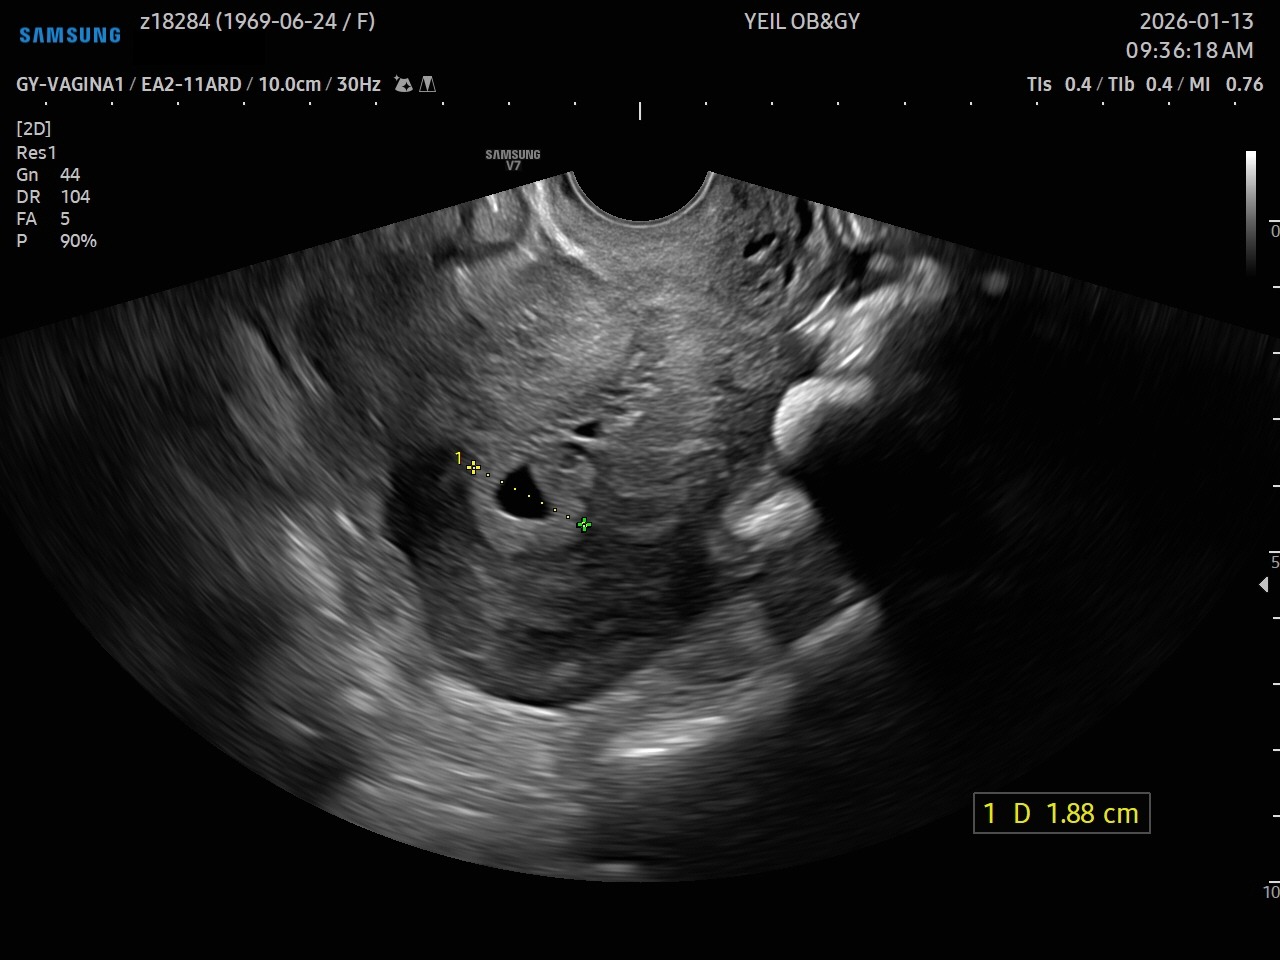

- 자궁내막암: 타목시펜을 5년간 투여할 경우 자궁내막암의 상대적 위험도가 2.2배 증가함.